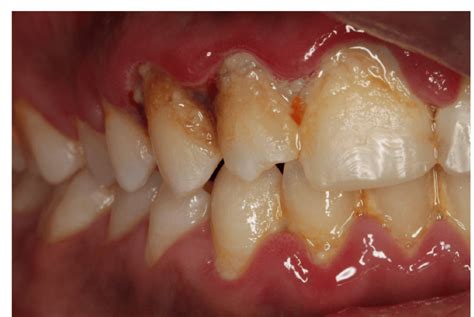

The classic symptoms often include redness and swelling of the gums. Instead of that healthy, firm pink tissue, your gums might look puffy, inflamed, and a vibrant, sometimes angry, red. This is your body’s natural response to irritation and inflammation caused by those pesky bacteria in plaque. Another major indicator is bleeding . If your gums bleed when you brush your teeth, even if you’re being gentle, or if you notice blood after flossing, that’s a big red flag. This bleeding happens because the inflamed blood vessels in your gums become more fragile and prone to rupture. You might also experience tenderness or soreness in your gums. They might feel sensitive to touch, or even just the pressure of eating can be uncomfortable. In some cases, the bacterial overgrowth associated with gingivitis can lead to bad breath (halitosis) . This is because the bacteria are producing volatile sulfur compounds, which we all know as that unpleasant mouth odor. So, if you notice any of these changes, especially if they appear suddenly, it’s definitely worth paying attention to.